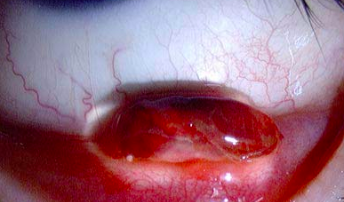

Pyogenic Granuloma

• Vascular tumor of skin or mucous membranes

• Rapid development

• Fibrovascular proliferative response to conjunctival injury

• Any age - children & young adults most common

• Causes

• Trauma

• Mechanical

• Surgical

• Infection

• Hormonal influences

• Idiopathic

• Treatment

• Steroids

• Excision